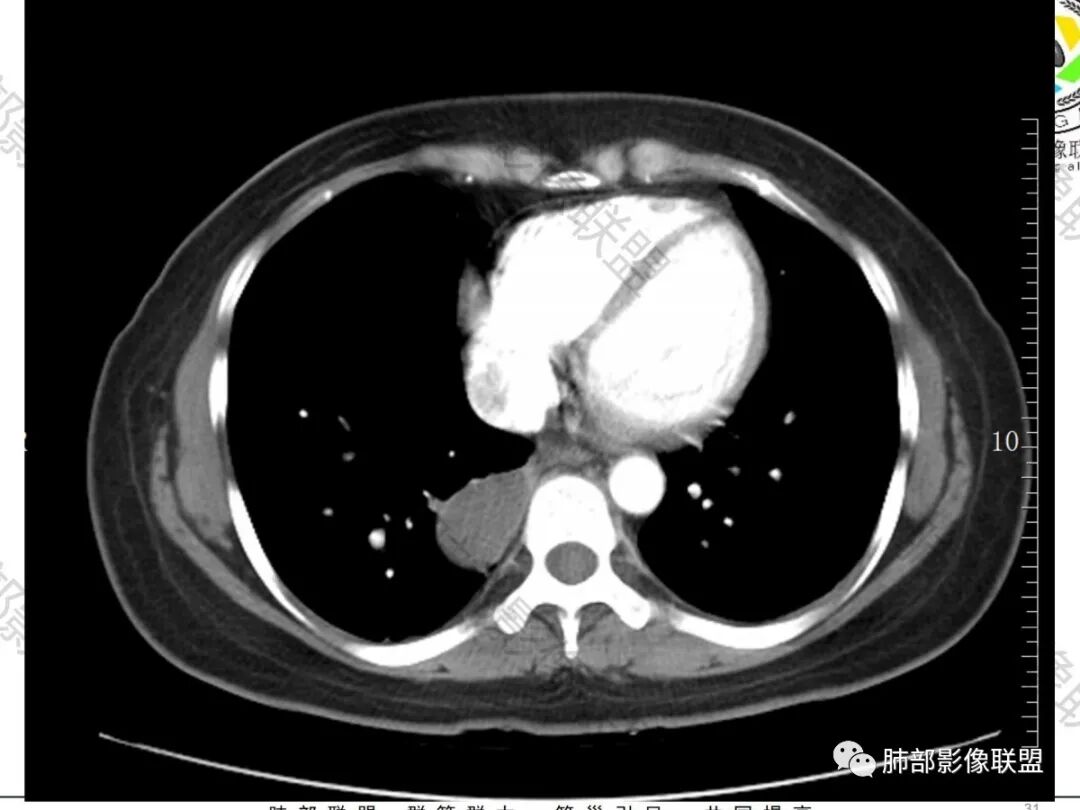

一切∮随缘:右肺下叶胸膜下肿块,宽基底与胸膜相贴,右侧胸水,平扫密度均匀,增强后囊性无强化,囊壁实性结节轻度强化,考虑:支气管囊肿,神经源性肿瘤囊变.

杨泽锋:病灶由两个部分组成靠后方近胸膜的为一囊性病灶,考虑支气管囊肿靠前方病灶为一实性软组织密度影,对囊性病灶形成了压迫,所以不是单纯的肺不张或者感染,应该有个占位性病变存在,看内部的血管还算自然,考虑良性病变,炎性肉芽肿可能大

飞鹰行动:右肺下叶胸膜下囊实性肿块,宽基底与胸膜相贴,内部密度均匀,增强后内部未见明显强化,实性结节轻度强化,相邻胸膜未见受侵犯,考虑良性病变,神经源性肿瘤囊变.其次支气管囊肿。

张慧:右肺下叶实变灶,宽基底、不规则,有少量胸腔积液。增强后边缘有强化,内部坏死(坏死不确定)。

考虑:良性病灶,结核可能性大。

看图说话:右肺下叶囊实性肿块,实性部分分叶,毛刺,轻度强化,囊性无强化,邻近胸膜增厚,脂肪间隙清晰,胸腔积液,考虑恶性,肉瘤,鉴别支气管囊肿感染。

晨:定位肺内,强化边缘有强化,内无强化,考虑支气管囊肿或包裹性积液?

harvey:右肺下叶胸膜下肿块,宽基底与胸膜相贴,平扫密度均匀,增强后内侧囊样无强化,考虑支气管囊肿可能性大

采莲:中年女性,因腹疼入院,血象不高,右肺下叶基底段靠近脊柱旁胸膜下肿块,由两部分组成,靠近胸膜下边缘较光滑,密度低,无明显强化,与胸膜宽基底相连,周围胸膜增厚,少量胸腔积液,胸膜下脂肪间隙清晰。靠外侧肿块密度高,有强化,考虑神经源性肿瘤?囊肿?患者腹疼不知道是否与病灶有关?

右肺下叶胸膜下肿块,宽基底与胸膜相贴,长轴与胸膜平行,胸膜下脂肪间隙清晰(定位胸膜),增强呈不均匀强化。另右肺上叶见小结节影,双侧胸腔少量积液,常规结核先考虑,鉴别肉瘤样癌、神经源性肿瘤。

一米阳光:年轻女性,右下肺胸膜下囊实性占位,边界清晰,囊性部分张力较高,实性部分密度均匀有分叶,胸膜下间隙清晰,增强后实性部分强化,囊性边缘强化。定位肺内,考虑支气管囊肿,鉴别结核,肉瘤样癌。

黄兴:定位:肺内,胸膜下脂肪间隙清晰右肺下叶胸膜下囊实性肿块,宽基底与胸膜相连,增强后实性结节轻度强化,胸水。考虑良性可能,支气管囊肿可能

流心明智:中年女性,腹疼入院。胸部CT:右肺下叶基底段胸膜下肿块,近脊柱,肺侧毛糙、胸膜侧平滑,病灶由两部分组成,尖顶部分密度较高且强化不均匀;基底部近胸膜侧边缘光滑、囊性,密度低且均匀,无明显强化,与胸膜宽基底相连,周围胸膜增厚,少量胸腔积液,胸膜下脂肪间隙清晰。考虑:肺和胸膜都有,胸膜结核瘤?支气管囊肿并感染?SFT?鉴别肉瘤样Ca、神经源性肿瘤等。